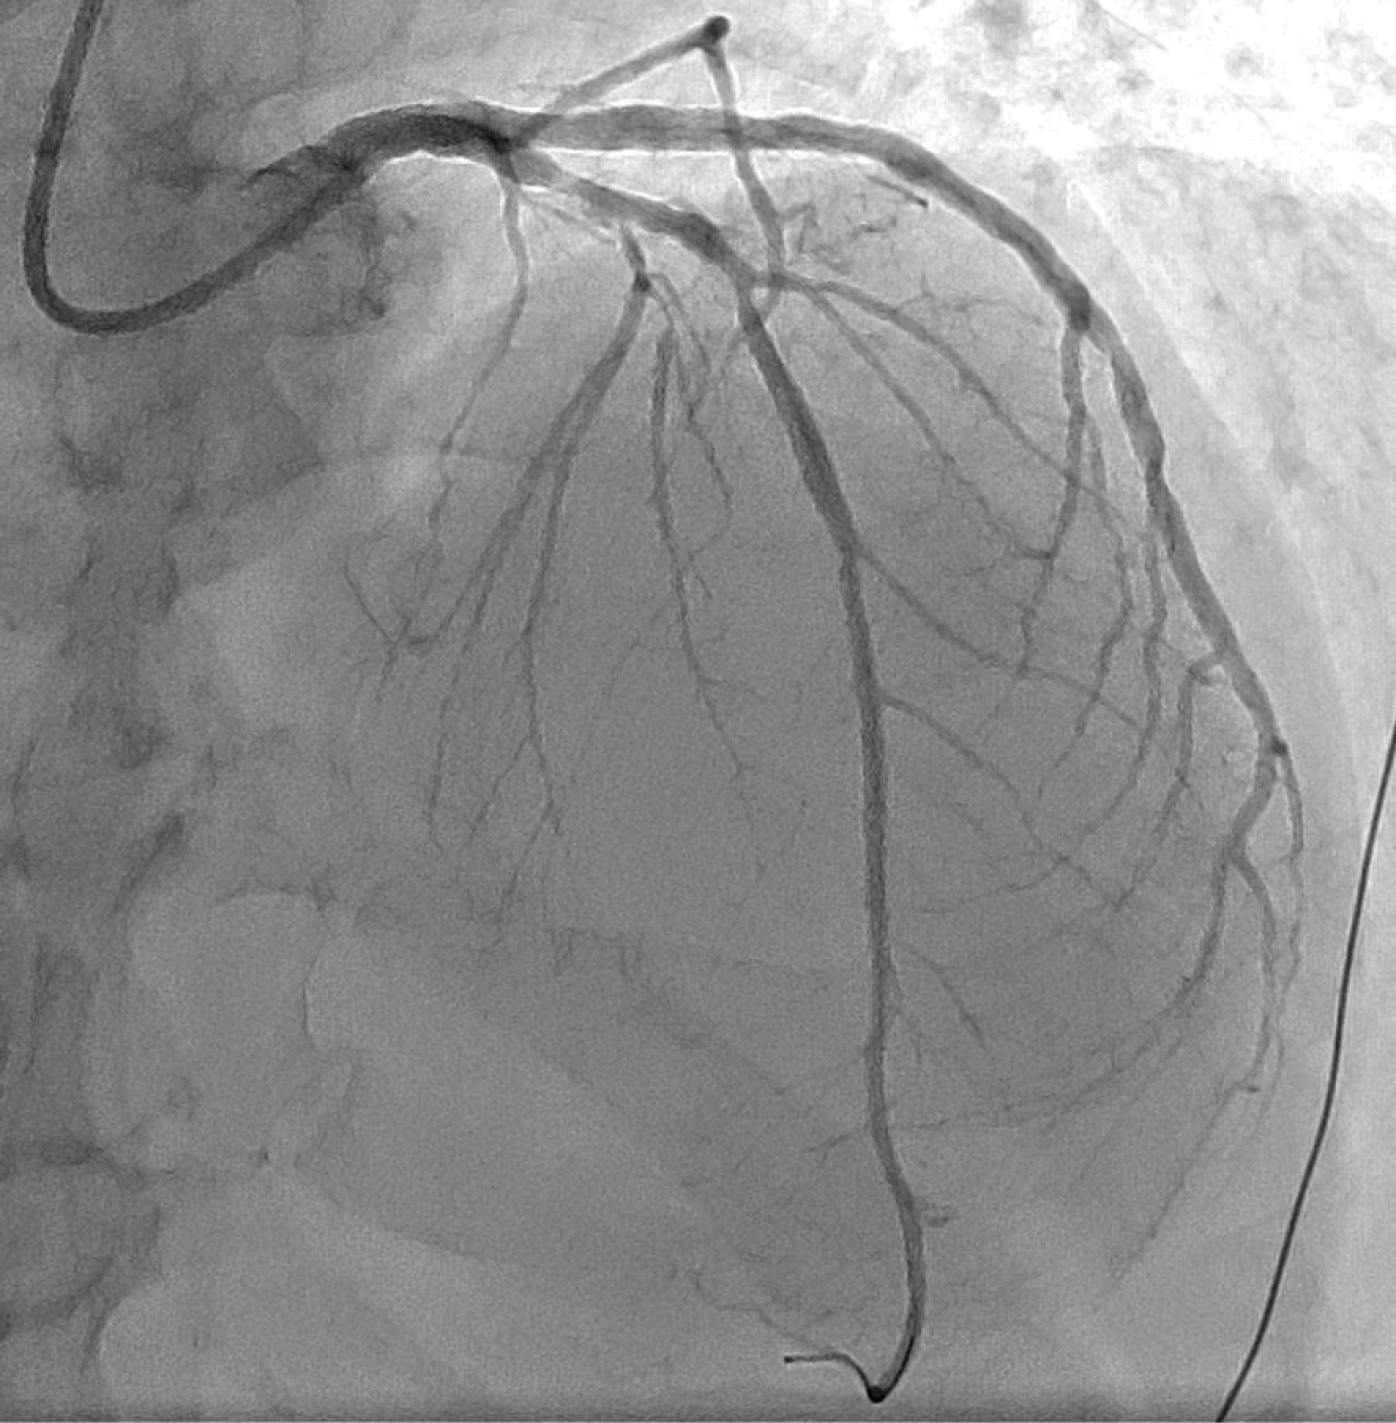

A male in his mid-60s, an ex-smoker and with type 2 diabetes mellitus, presented to the emergency department with a 2-hour history of de novo typical chest pain at rest. The 12-lead electrocardiogram showed an anterior STEMI. The patient was transferred to the catheterization laboratory for primary PCI after receiving intravenous loading doses of aspirin (250 mg) and unfractionated heparin (5,000 IU). The coronary angiogram demonstrated an acute thrombotic occlusion of the proximal LAD with high thrombus burden (TIMI thrombus grade 5) (Figure 1).

Figure 1. Coronary angiogram showing an acute thrombotic occlusion of the proximal LAD with a high thrombus burden.